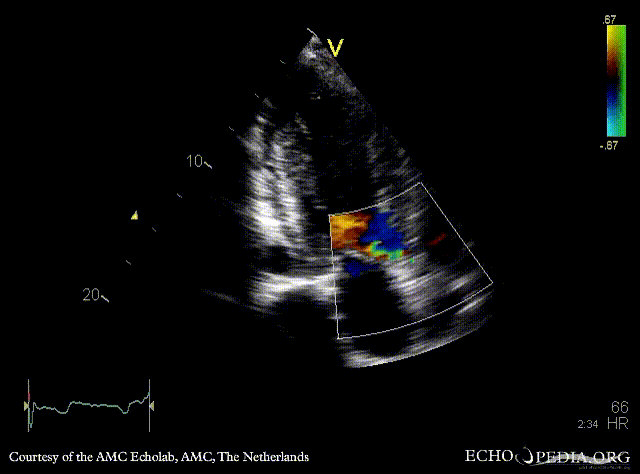

Subvalvular membrane in left ventricle outflow tract

PLAX: subvalvular membrane in left ventricle outflow tract PLAX with Color Doppler: high velocity flow in left ventricle outflow tract